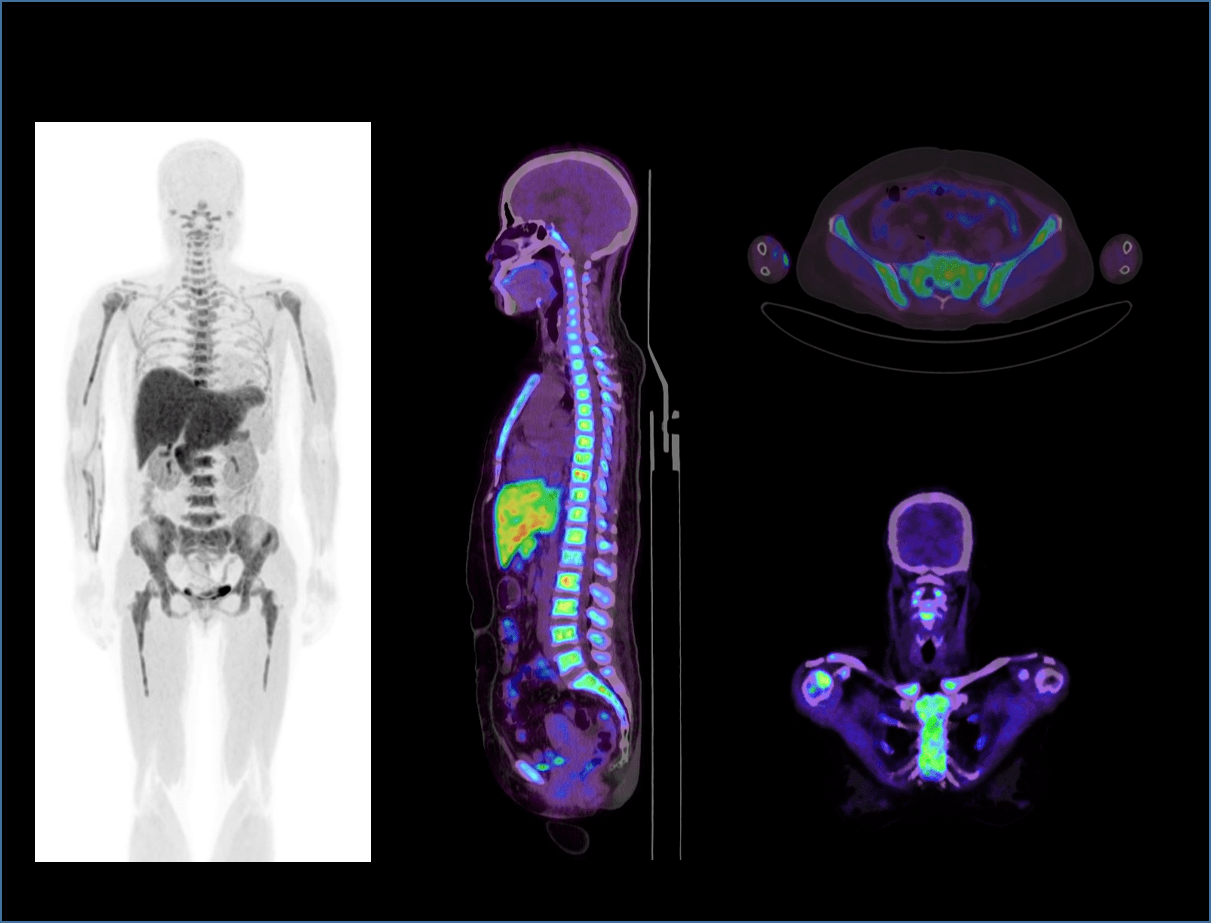

Ultra-large axial FOV를 통한 Whole organ 이미징

eye-to-thigh 스캔

전신 스캔 시 5분 이내의 신속한 속도로 진행